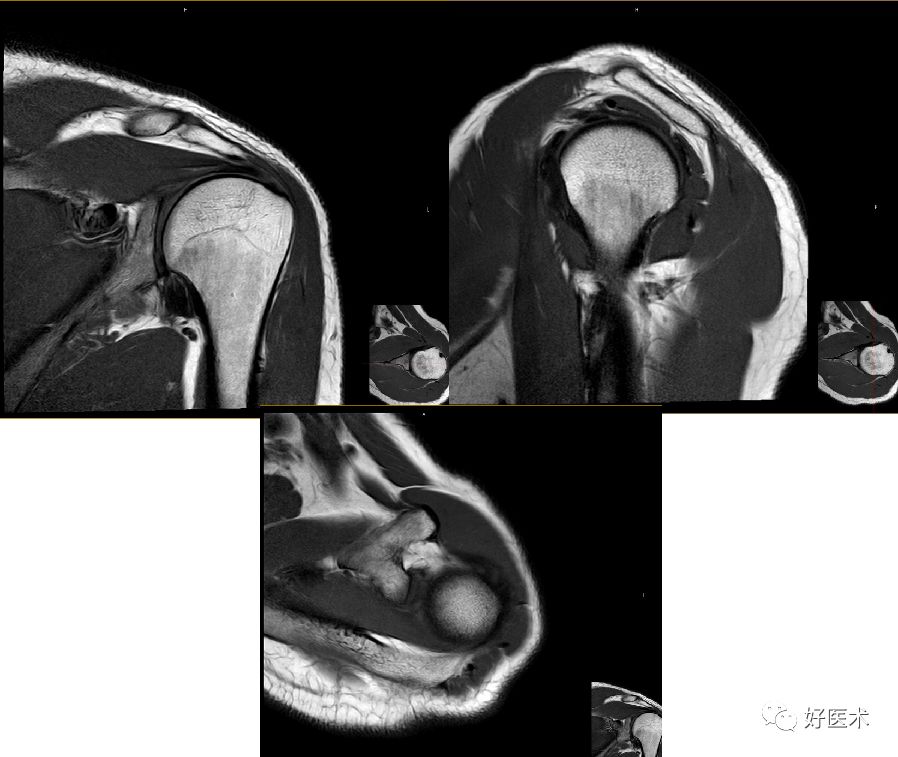

肩峰撞击综合征MR表现

肩峰下滑囊炎

-

T1WI-滑膜囊增厚呈低信号,高信号脂肪层消失;

T2WI-滑膜增生、炎症渗出呈高信号

肩袖病变

Ⅰ期:T1W及PD上冈上肌在其附着处出现增高的信号影

Ⅱ期:肩袖变薄或不规则,肌腱内信号强度增加

Ⅲ期:肌腱的连续性中断或伴有增高的信号累及关节面

骨结构改变

主要为肩峰退行性病变:T1WI及T2WI见低信号的骨赘影

正常冈上肌MRI表现

肩峰撞击综合征的MR表现

冈上肌变性

肩袖信号增高

冈上肌关节面部分撕裂

滑囊面部分撕裂

冈上肌完全撕裂

冈上肌全层撕裂伴肩撞(骨赘形成)

冈上肌全层撕裂MRI间接关节造影表现

冈上下肌撕裂